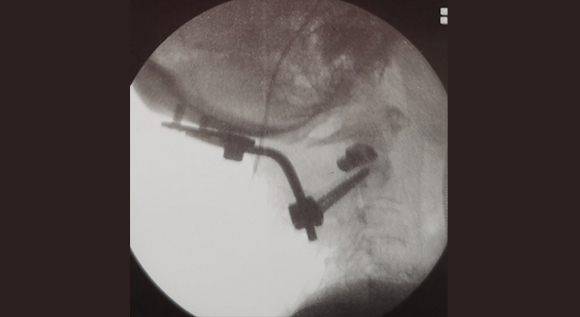

脊柱脊髓神經(jīng)微創(chuàng)中心以微創(chuàng)技術(shù)為引領(lǐng),以功能恢復(fù)為目標(biāo),主要治療脊柱外傷、腫瘤、退行性病變、脊柱畸形等疾病。團(tuán)隊(duì)利用神經(jīng)外科顯微技術(shù),結(jié)合神經(jīng)內(nèi)鏡微創(chuàng)技術(shù),對(duì)脊柱間盤變性疾病、頸腰椎管狹窄、頸腰椎間孔狹窄、頸腰椎間盤突出、頸腰椎體不穩(wěn)、脊柱骨折、寰樞椎脫位、脊柱腫瘤、椎管內(nèi)腫瘤、脊髓損傷、脊髓空洞、脊髓栓系等疾病進(jìn)行高效、特色手術(shù)治療,如顱頸交界區(qū)畸形寰枕減壓內(nèi)固定術(shù)、脊柱腫瘤全脊椎切除內(nèi)固定術(shù)、微創(chuàng)椎管內(nèi)腫瘤切除術(shù)、微創(chuàng)脊柱旁腫瘤切除術(shù)、寰樞椎脫位椎間融合內(nèi)固定術(shù)、脊柱骨折微創(chuàng)經(jīng)皮椎弓根釘內(nèi)固定術(shù)、經(jīng)椎間孔椎間融合內(nèi)固定術(shù)(MIS—TLIF)等,最大程度降低脊柱脊髓手術(shù)創(chuàng)傷,具有創(chuàng)傷小、輸血少、恢復(fù)快、口碑好,出院早等優(yōu)勢(shì)。